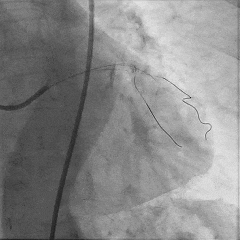

于LAD近中段植入Tivoli 2.75*33mm支架一枚,高压球囊后扩张后,血流TIMI3级

Sion导丝至LCX远端,预扩球囊扩张后,植入支架XIENCEAlpine 2.25*23mm支架一枚

术后造影支架膨胀良好,血流TIMI3级

1.本例患者三支病变,RCA及LCX为简单病变,LAD为CTO病变,本例患者成功开通前降支CTO病变,在合理评估患者冠脉病变的基础上,同时对RCA及LCX病变进行了治疗,“一箭三雕,毕其功于一役”,减少了患者进行介入手术次数及残余风险。

2.对于前降支CTO病变,本例患者首先尝试逆向开通,发现逆向侧枝循环均重度迂曲导丝无法通过。尝试逆向开通未果后,在逆向造影指引下,采用平行导丝、正向导丝升级技术进行正向开通,顺利送入D2#进而通过LAD闭塞段,通过逆向造影证实远端位于真腔,成功完成前降支CTO病变的治疗。